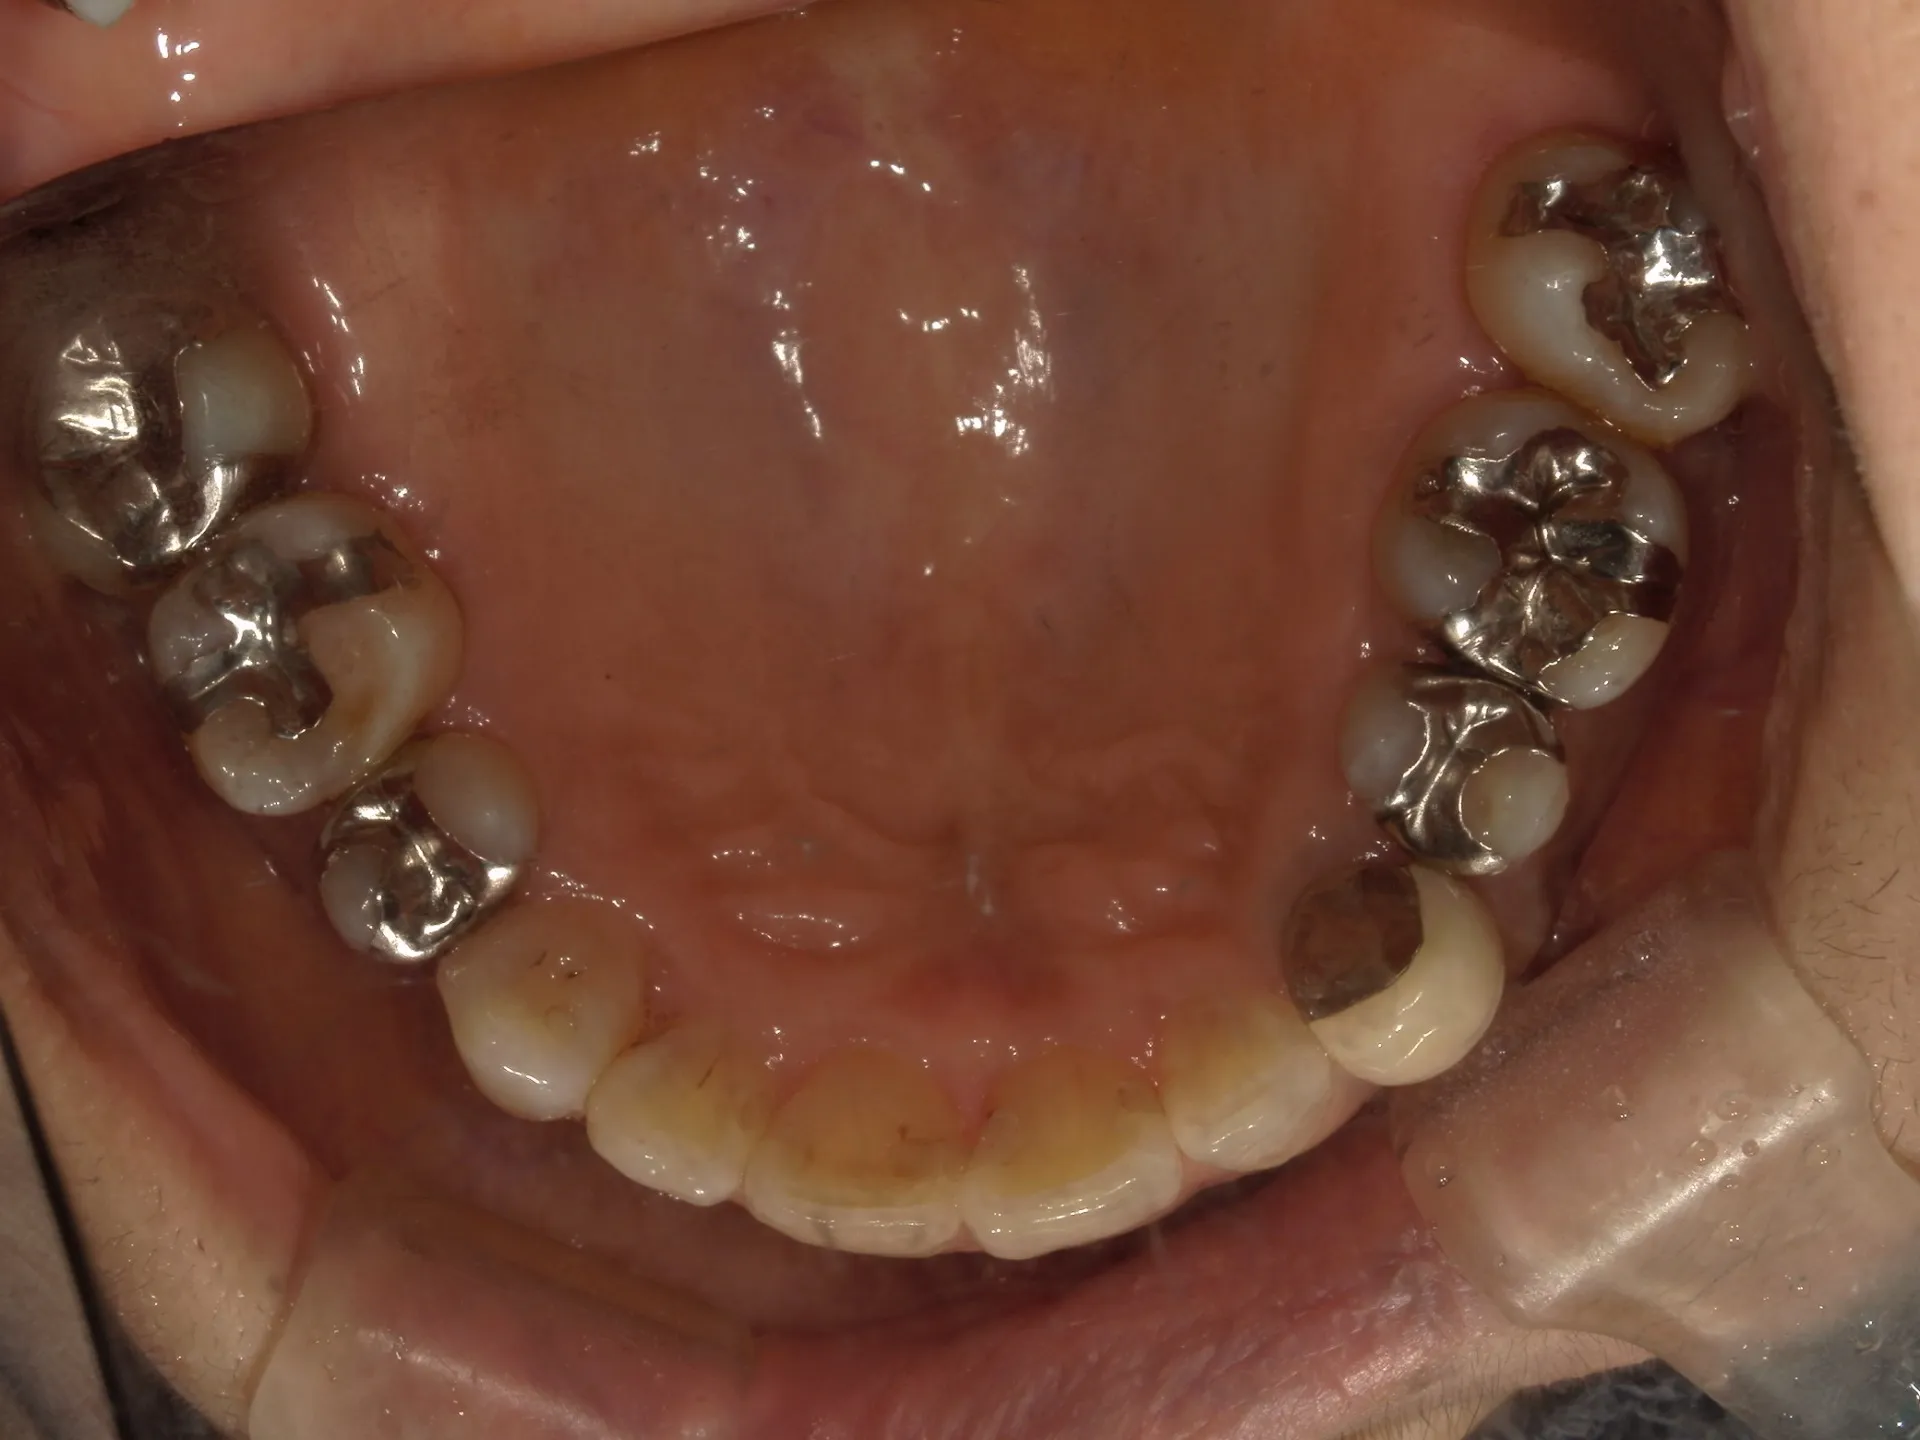

今回は65歳以上でも矯正治療を開始した症例についてご紹介いたします。

しかし、年齢がたとえ定年を迎えたあとであっても十分に矯正が行えて、今後の歯磨きが容易になり、虫歯や歯周病のリスクが減らせて歯を残すことが出来たり、歯並びが良くなったことでモチベーションも上がるなどの矯正後のメリットも非常に高いため、健康的な生活を行う上でも矯正治療は行うことをお勧めします。